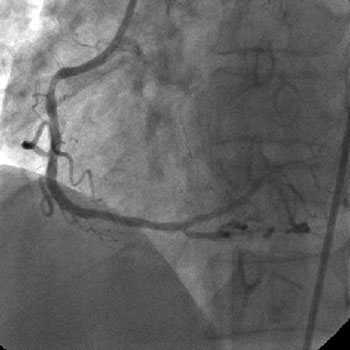

Angiography

1) RCA: Discrete severe mid stenosis (Figure 1)

2) LCX: 50% proximal tubular stenosis

3) LAD: Ostial CTO ( Figure 2) with collaterals from RCA and LCX (Figure 3).